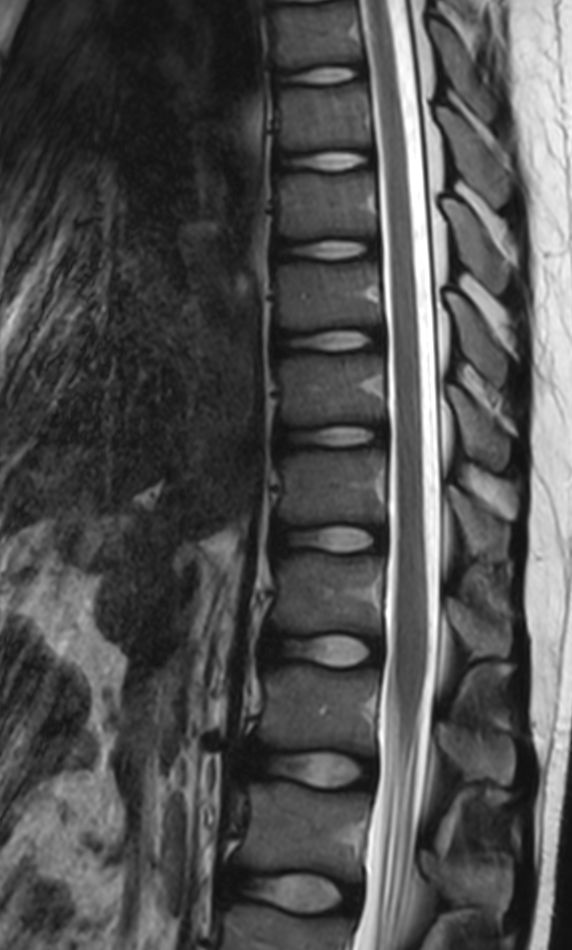

Sagittal T2w TSE (T-Spine)

Sagittal T2w TSE (L-Spine)

Sagittal T1w TSE (T-Spine)

Sagittal T1w TSE (L-Spine)